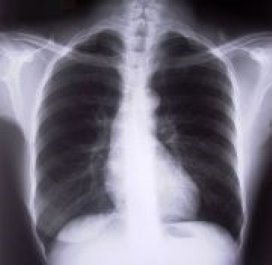

Een longontsteking is al te verhelpen met een antibioticakuur van drie dagen. De gebruikelijke kuur van zeven tot tien dagen blijkt volkomen onnodig.

Dat concluderen onderzoekers van het AMC. Internist Jan Prins ontdekte dat longontstekingen